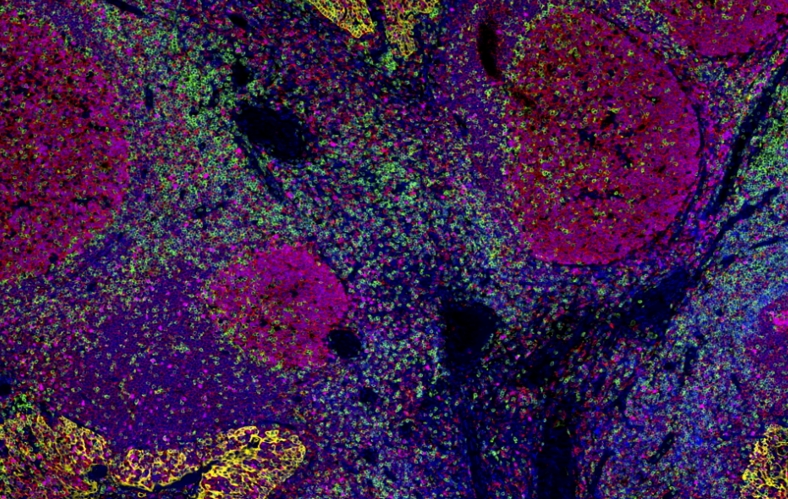

多重荧光免疫组化

多重荧光免疫组化系列产品